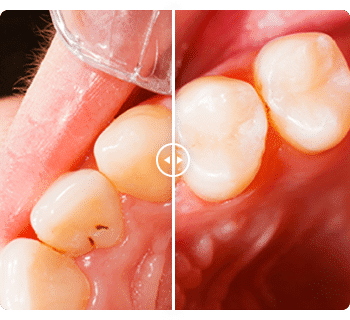

BEFORE AND AFTER

Before and after dental photos

To see what a smile makeover can accomplish, take a look

at our dentistry before and after photos.